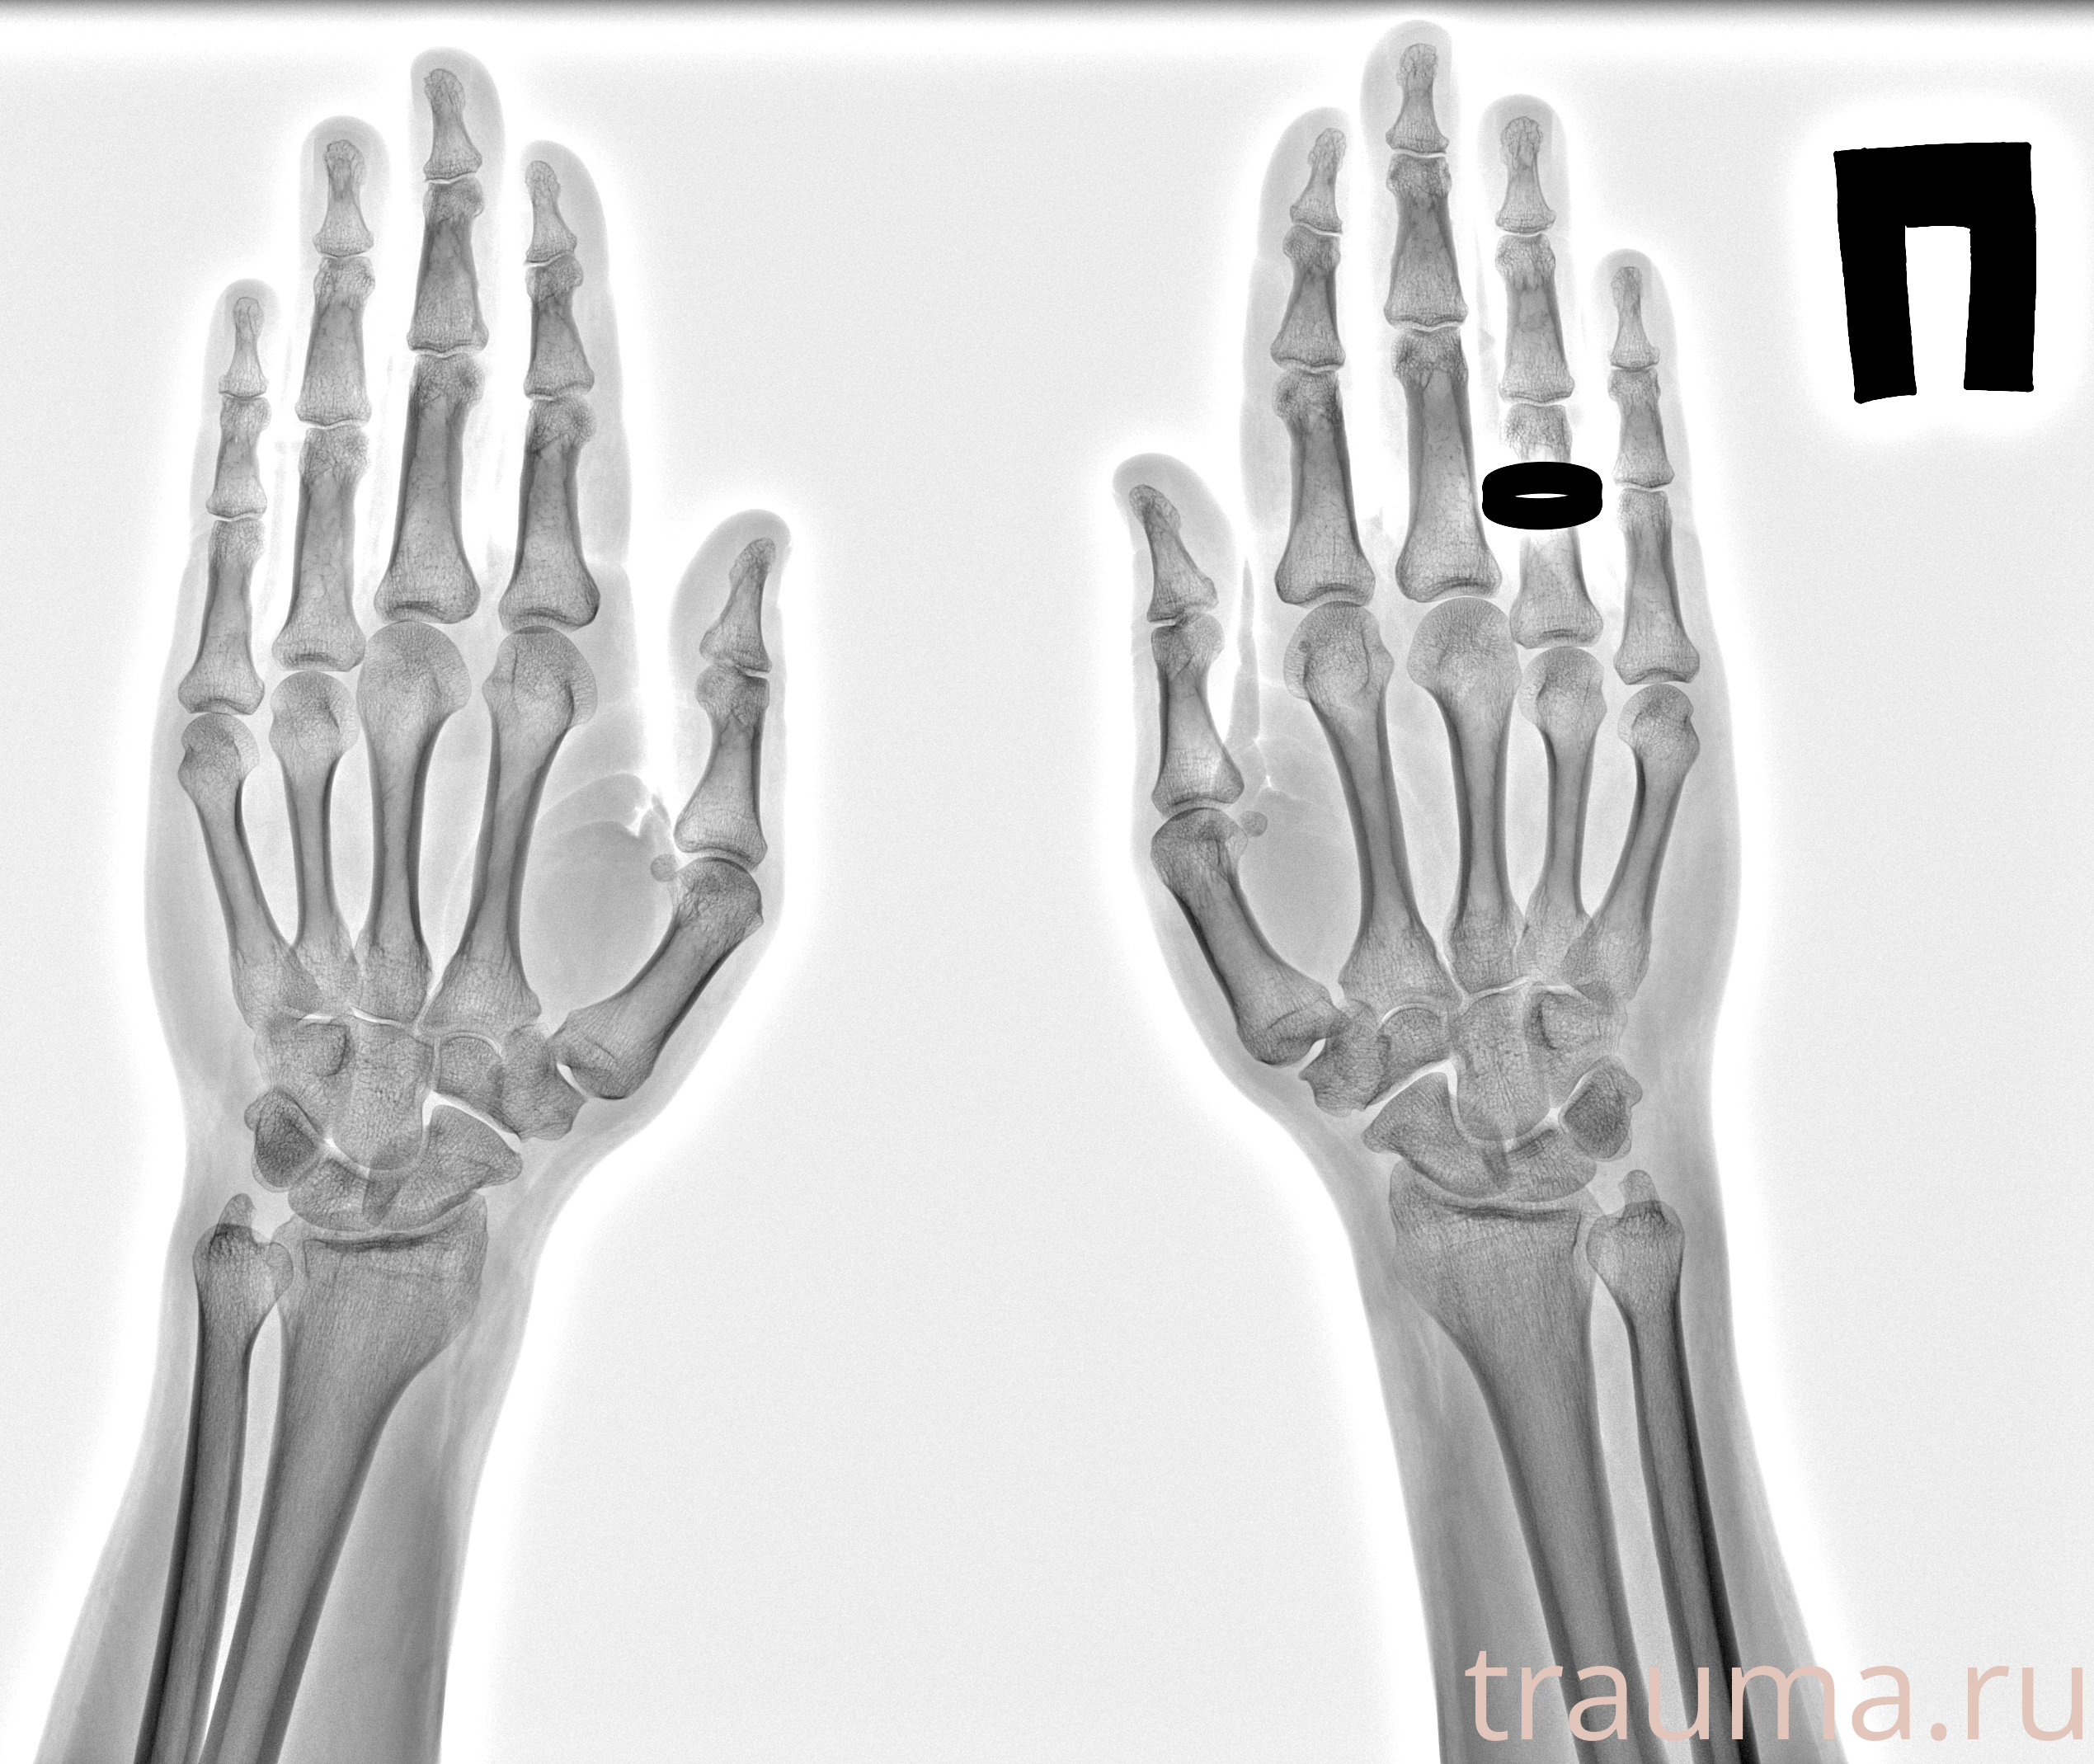

Рентгенограммы

Рентген на дому: по вашему адресу приезжает врач-рентгенолог, травматолог-ортопед с мобильным рентгеновским аппаратом, проводит диагностику травмы или заболевания, делает необходимые рентгенограммы, дает рекомендации по дальнейшему лечению. Получить качественные снимки в домашних условиях возможно благодаря уникальной методике, разработанной МосРентген Центром для института  Склифосовского